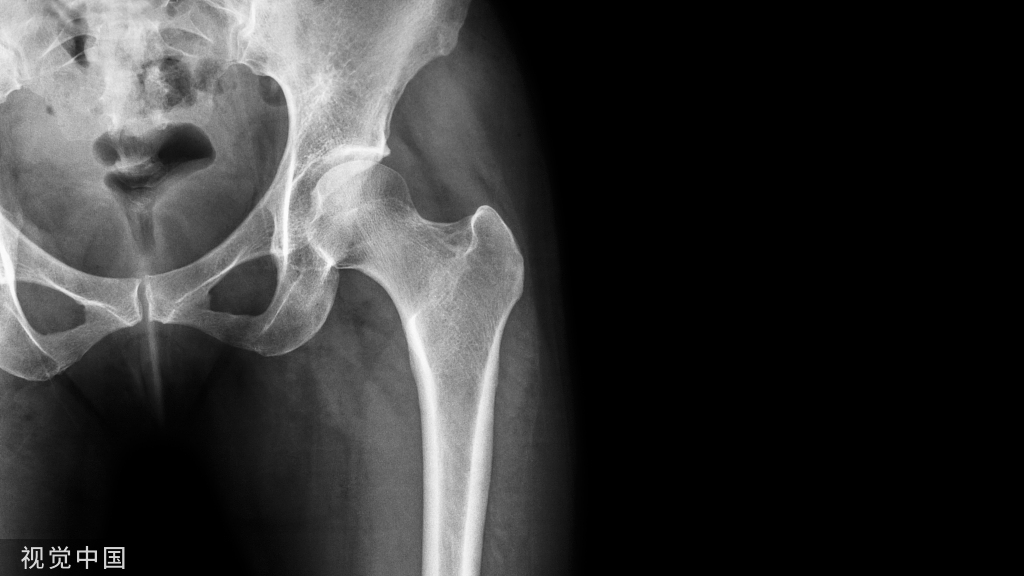

粗隆间骨折好发于老龄患者,为三大骨质疏松性骨折之一,通常需采用内固定治疗。粗隆间骨折内固定的选择,与骨折类型密切相关。关于小转子及内侧壁的重要性,已经越来越受到重视,部分内固定的失效也与其相关。有学者研究了粗隆间骨折累及小转子及内侧壁的大小与内固定失效的关系,结果发表在Injury期刊上。

I型:小转子撕脱骨折;骨折线不超过小转子基底部;

II型:小转子基底部附近累及后内侧皮质;骨折线未达到后壁中线;

III型:累及后内侧皮质;骨折线达到或超过后壁中线。

图1 病跟依据小转子骨折累及的后内侧皮质范围,将其分为三型。例挑选与治疗方法流程图。